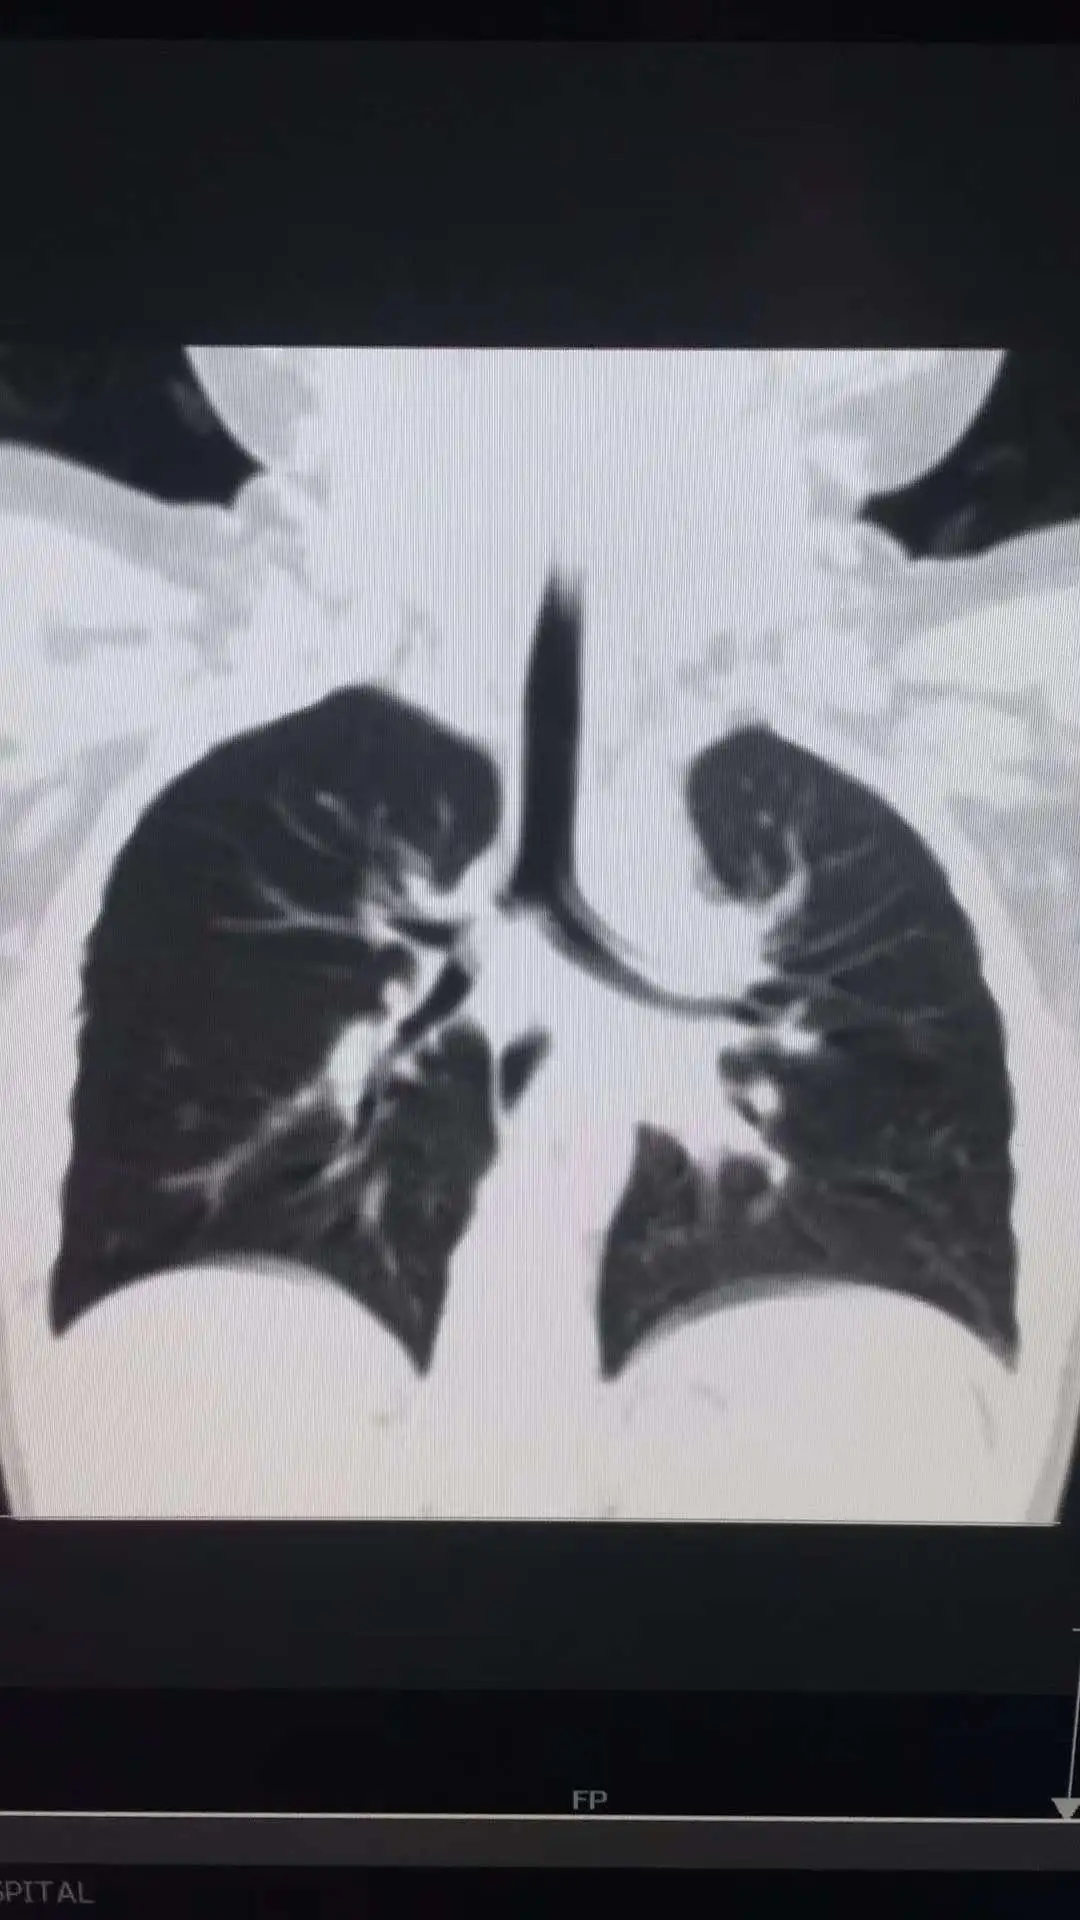

转机出现在一次常规胸部CT检查中。细心的医生发现乐乐右主支气管内有密度较高阴影,且伴随明显肺气肿,高度怀疑支气管异物,当即建议转诊至市儿童医院儿童呼吸科进行呼吸内镜检查。“儿童气道狭窄,异物长期滞留不仅会引发反复感染,还可能导致肺脓肿、支气管扩张等严重并发症,甚至危及生命,必须尽快明确诊断并干预。”该院儿童呼吸科主任任晓红介绍。

接诊后,医院第一时间启动多学科联合诊疗,儿童呼吸科、麻醉手术科、医学影像科、儿童重症医学科专家共同会诊,快速完善术前准备。手术采用全麻方式,医生操作直径仅2.8毫米的超细支气管镜,缓缓通过乐乐声门插入气管。借助支气管镜的高清照明和摄像头,显示器上清晰呈现出“罪魁祸首”——一颗已部分碎烂的葵瓜子紧紧卡在右主支气管内,周围已长出肉芽组织。